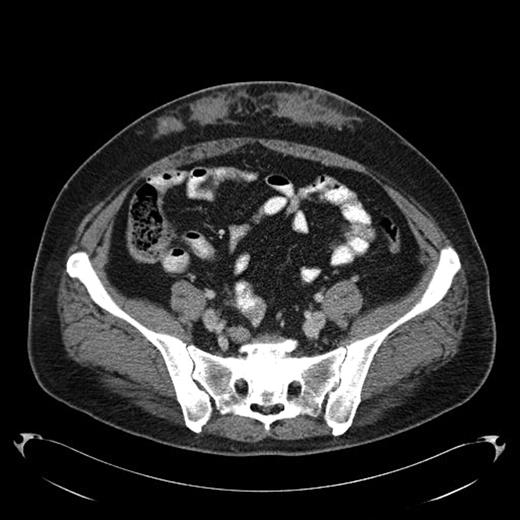

A 43-year-old female diagnosed with diabetes mellitus in 1986 after acute pancreatitis secondary to hypertriglyceridemia presented to our hospital in December of 2008 with a 2 year history of low grade fever of 99-100F. This was associated with chills and fatigue. Over the same time period she had noticed anterior abdominal wall nodularity, particularly at sites where she has been injecting her insulin. Her insulin requirement had also increased from a total of 60 units of NPH in a day to 170 units per day. Because of the subcutaneous nodularity at the site of injection a decision was made to switch the site of the insulin which resulted in lower blood glucose level and subsequently significant decrease in her insulin requirement to 120 units a day. This suggested poor absorption from the infiltrated site. At our clinic laboratory data showed normal white count of 5.4 × 10(9)/L with normal differential, normal hemoglobin of 12.9 g/dL with an ESR of 11 mm/hour, creatinine of 0.8 mg/dL and C-reactive protein of less than 3. As part of the work up for fever of unknown origin a CT-scan of the abdomen was obtained which showed infiltrative lesion in the anterior abdominal subcutaneous tissue with few calcifications Fig 1 & 2. Biopsy of the anterior abdominal wall nodular infiltrate was performed. Tissue cultures came out negative for infection. The biopsy showed eosinophilic material positive with Congo red staining and showing apple green birefringence when viewed under polarized light. Immunohistochemical staining showed this to be negative for AA, AL, or TTR amyloidosis. Liquid chromatography tandem mass spectrometry (LC MS/MS) detected peptides representing apolipoprotein E, apolipoprotein A-IV, SAP and Insulin. The amyloid deposits stained positive with anti-insulin. The presence of peptides from insulin and immunohistochemical reactivity with an anti-insulin antibody indicated that the amyloid deposits were caused by insulin injection at this site. Work up for systemic amyloidosis including serum protein electrophoresis with immunofixation was negative for a monoclonal protein. Quantitative immunoglobulins were within normal range. Her 24-hour urine protein was 65 mg within normal range. Her serum free light chains were unremarkable. Echocardiogram did not show any evidence of infiltrative cardiomyopathy. This was therefore consistent with localized insulin induced cutaneous amyloidosis. The recommendation was to change the insulin type and to rotate the insulin injection site. Because of occasional hemorrhage and pain the long term plan will be to surgically remove the amyloid deposits.

Fig 2.

Amyloid infiltration in subcutaneous tissue of lower abdomen at insulin injection site